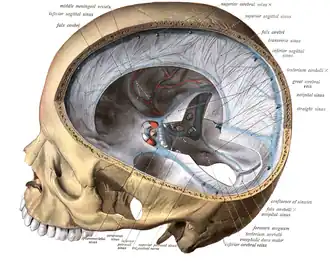

Illustration of the dural venous sinuses | |

Dural venous sinuses | |

Dura mater and its processes exposed by removing part of the right half of the skull, and the brain.

Dura mater and its processes exposed by removing part of the right half of the skull, and the brain. -